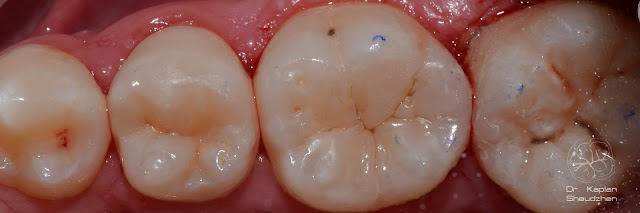

Каплан Опубликовано 26 марта, 2017 Автор Поделиться Опубликовано 26 марта, 2017 Давно что-то ничего не публиковал тут... Так что простите за спам )) все выполнено одним цветом GC Essentia Universal. 3 Ссылка на комментарий

Каплан Опубликовано 26 марта, 2017 Автор Поделиться Опубликовано 26 марта, 2017 2 часа от вкола. Не идеально. валики надо чуть дисками подправить. оставили коррекцию на след. визит, когда будем лечить 5 и 7. 2 Ссылка на комментарий